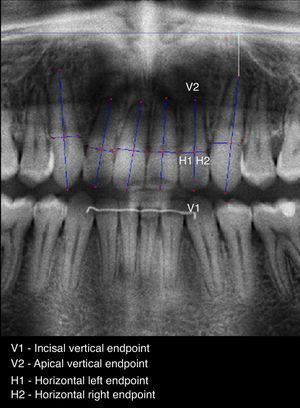

To allow a standardized and accurate method for measuring EARR, a software prototype (ARIAS – Apical Resorption Image Analysis System) in MATLAB version 7.12.0.635 (R2011a) was developed. The proposed method includes the following three steps: (1) image preprocessing, allowing the application of image enhancing filters; (2) point selection, manually marking 4 points on each selected tooth: two points, V1 and V2 (the vertical points) defining a vertical line segment outlining the intersection between root and crown, and two points H1 and H2 (the horizontal points) defining a horizontal line segment that represents the tooth width (Figs. 1 and 2) and (3) feature extraction, to automatically produce a set of linear measurements in T1 and T2 radiographic images, such as: initial root length (R1), initial crown length (C1), final root length (R2), final crown length (C2) and corrected final root length (CR2) – Table 1.